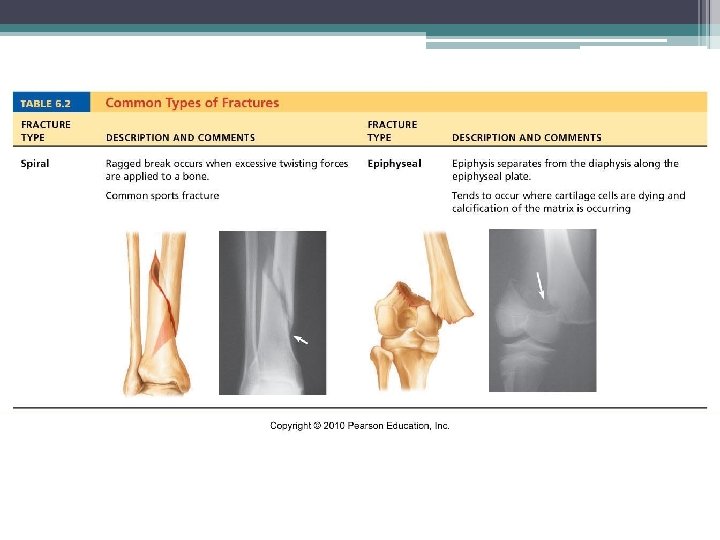

Fractures (Breaks) Classified by: 1. Position of bone – nondisplaced (normal) or displaced (bone out of alignment) 2. Completeness of break – complete (broken through) or incomplete 3. Orientation to long axis of bone – linear (parallel to bone) or transverse (perpendicular to bone) 4. If bone penetrates skin – open (compound) fracture or closed (simple) fracture